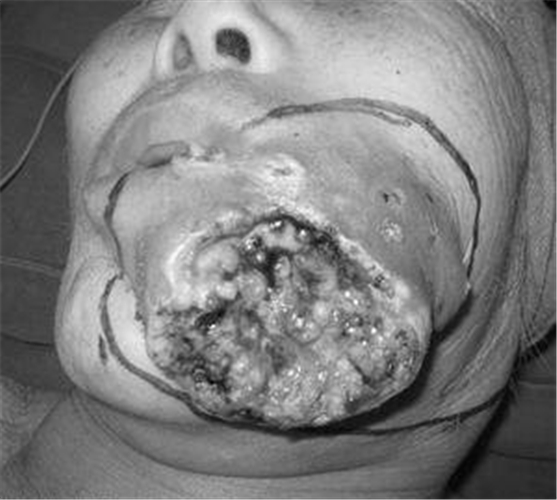

女性頰癌潰爛

女人頰癌潰爛